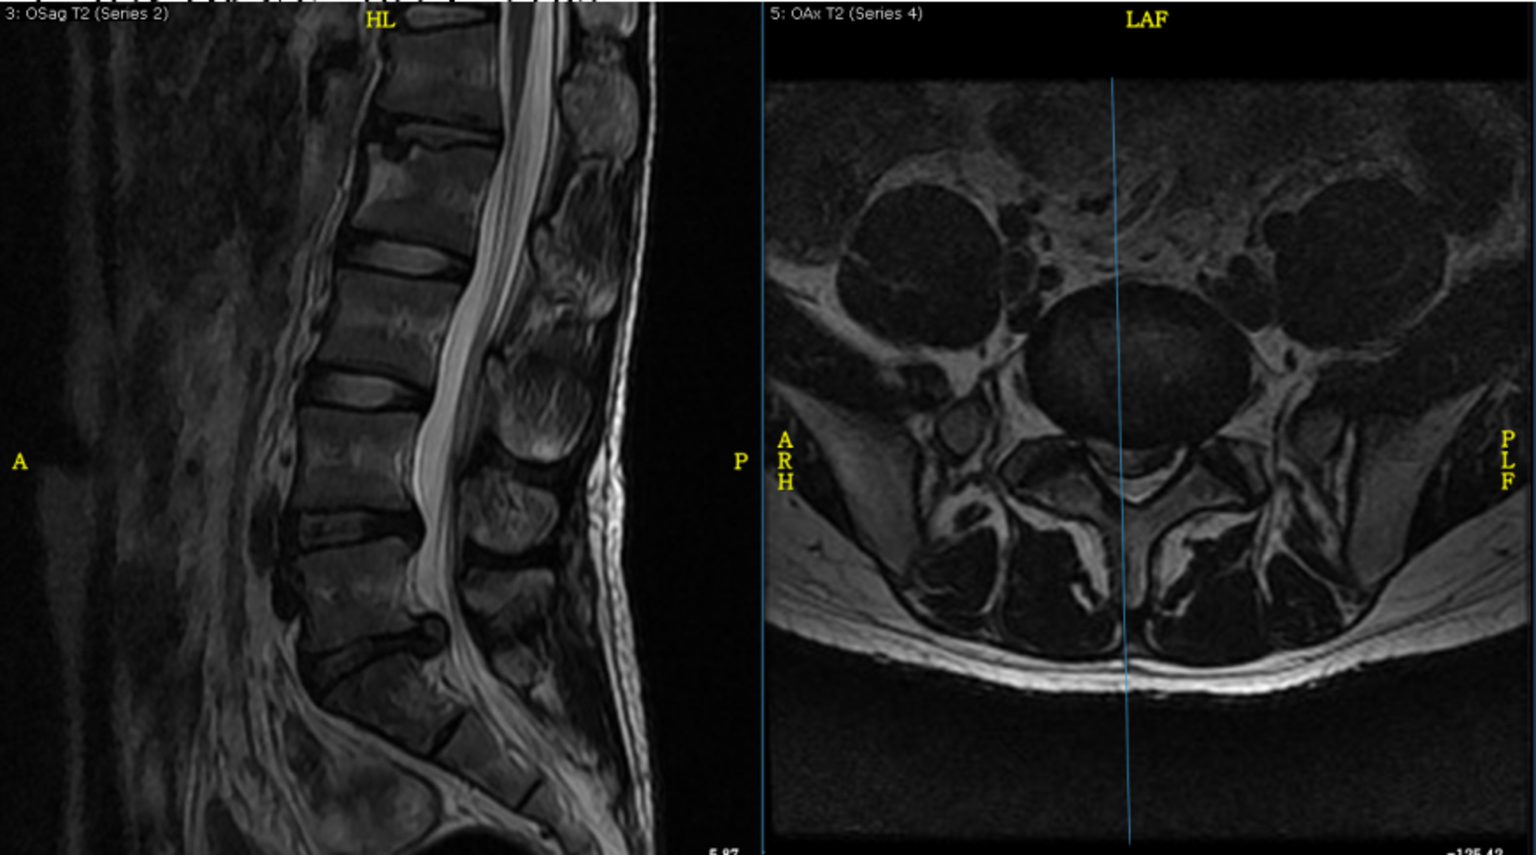

葛志田 男 48岁 l5/s1椎间盘突出症

腰椎磁共振检查,显示l4/l5,l5/s1椎间盘突出,两个腰椎髓核脱出压迫到